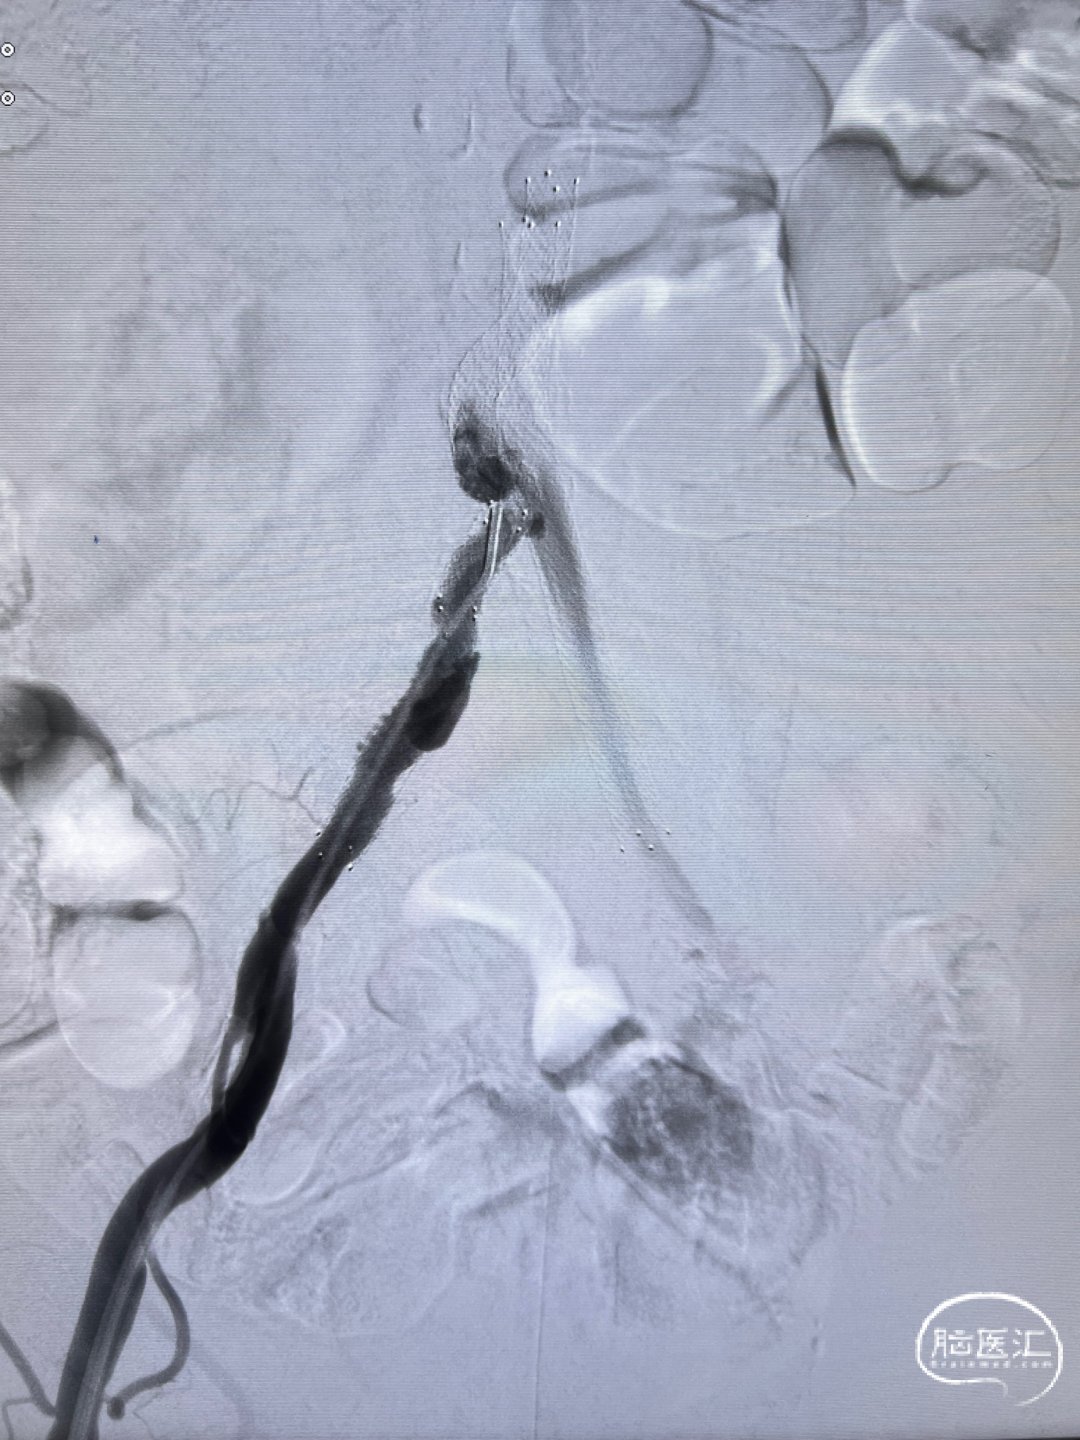

经桡入路完成全脑血管造影:主动脉弓。

右侧颈内动脉闭塞。

左侧颈内动脉重度狭窄,左侧大脑中动脉闭塞,通过前交通动脉向右侧大脑中动脉供血区代偿。

后循环造影。

通路建立:经右侧桡动脉近桡穿刺,在赛诺APEX TRA GC™ SIM2-130cm内管的指引下将赛诺APEX TRA™ 6F 95cm经桡远端通路导引导管送行到颈总动脉末端。

5mm保护伞顺利到位,系统稳定。

5×30mm 扩张球囊到位,球囊扩张过程系统稳定。